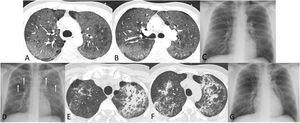

A 41-year-old man who presented to our hospital with fever and dyspnea was found to be severely immunosuppressed due to advanced human immunodeficiency virus (HIV) infection. Computed tomography (CT) demonstrated extensive ground-glass opacities (Fig. 1A, B), whereas a bronchoalveolar lavage (BAL) confirmed a Pneumocystis jirovecii infection. The patient responded (Fig. 1C) to cotrimoxazol and was discharged 2 weeks later after being started on antiretroviral therapy (ART). However, he was re-admitted 3 days later with fever and chest discomfort. A chest radiograph showed new-onset bilateral consolidations (Fig. 1D). CT confirmed large peribronchial consolidations with bronchial lumen dilatation (Fig. 1E, F), so a presumptive diagnosis of Pneumocystis jirovecii-immune reconstitution inflammatory syndrome (PJ-IRIS) with a CT pattern of organizing pneumonia (OP) was made. A repeat BAL did not yield any microorganism. The patient was treated with high doses of prednisolone (80mg/day) and rapidly improved clinically and radiologically (Fig. 1G).

(A) and (B) Axial thoracic CT images (lung window) show extensive ground-glass opacities in both lungs, consistent with Pneumocystis jirovecii pneumonia. (C) Posteroanterior chest radiograph performed on the day of discharge shows resolution of opacities after treatment with cotrimoxazol and prednisolone. (D) Three days after being discharged, a repeat chest radiograph shows new-onset bilateral consolidations (arrows). (E) and (F) Axial thoracic CT images (lung window) show large peribronchial consolidations with bronchial lumen dilatation, a pattern typical of organizing pneumonia. (G) Posteroanterior chest radiograph performed one month after (D) shows an almost complete resolution of the pulmonary opacities.

PJ-IRIS occurs within days to weeks after the initiation of ART, as the exaggerated CD4 inflammatory response causes severe lung injury.1PJ-IRIS may clinically manifest in the same way as Pneumocystis pneumonia (dyspnea, cough, and profound hypoxia), and patchy or diffuse ground-glass opacities are typically seen on imaging.1 Very rarely, PJ-IRIS may show CT features of OP, as in our case.2